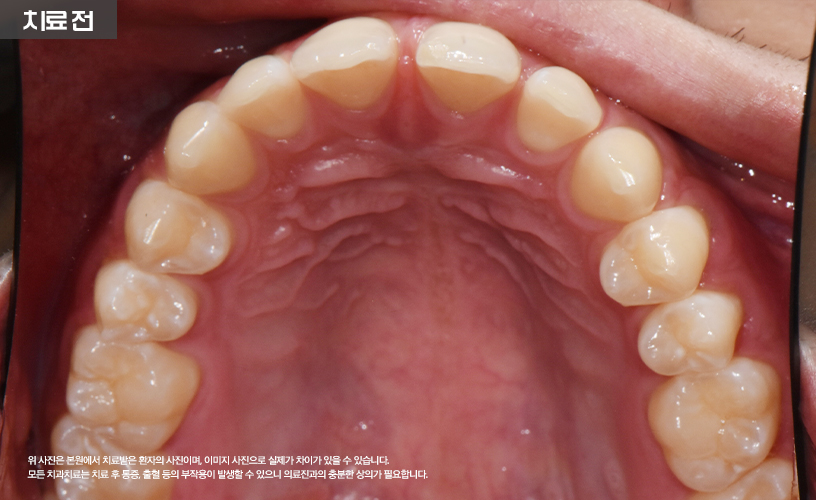

"투명교정 치료 사례"

상기 환자분은 상, 하악 앞니 벌어짐으로 인해

교정 치료를 고민하시다가 본 원에 내원하셨습니다.

본 원에서는 정밀한 검진을 통해 환자분의

앞니 벌어짐 상태를 점검한 다음

기존 일반적인 교정 치료 방식이 아닌

시스루 얼라이너 투명교정 치료가 수립되었습니다.

본 원에서는 교정 치료 시 디지털 구강 스캐너와

3D 프린터를 활용하여 치료가 진행됩니다.

또한 투명한 강화 플라스틱으로 맞춤 제작되므로

다른 교정장치에 비해 티가 잘나지 않아